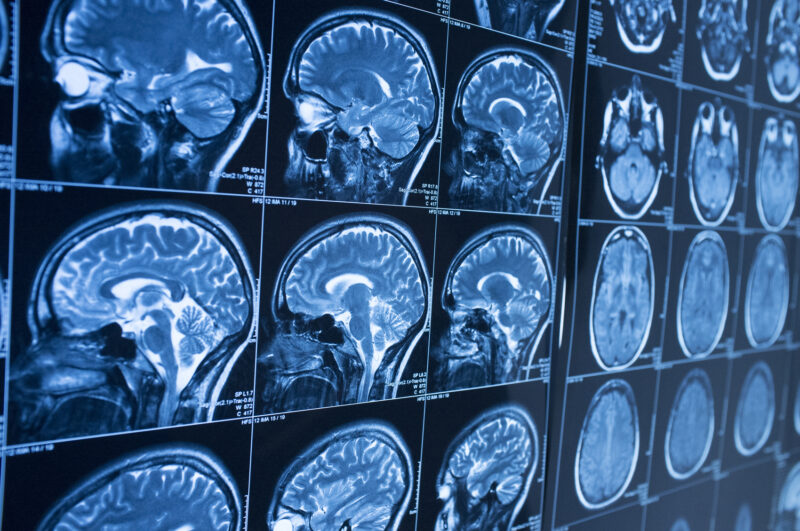

Blunt force head trauma can affect the brain in several different ways. Doctors use imaging tests and neurological evaluations to identify the specific type of injury. Types of blunt force head injuries commonly include:

Doctors use a combination of physical examinations, neurological assessments, and imaging studies such as CT scans or MRIs to diagnose head trauma. Treatment depends on the type and severity of the injury.